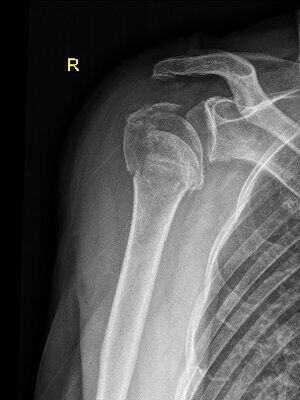

Oberarmbrüche (Frakturen)

Um eine klares Verständnis der individuellen Anatomie zu bekommen ist heutzutage eine präoperative Planung in der Endoprothetik unerlässlich. Auch in der Frakturversorgung ist es mir speziell wichtig, bereits vor der Operation einen genauen Plan zu haben um Größe und Ausrichtung des Implantates zu bestimmen. Nur dann kann man Unvorhergesehenes minimieren um ein optimales Ergebnis zu erzielen.